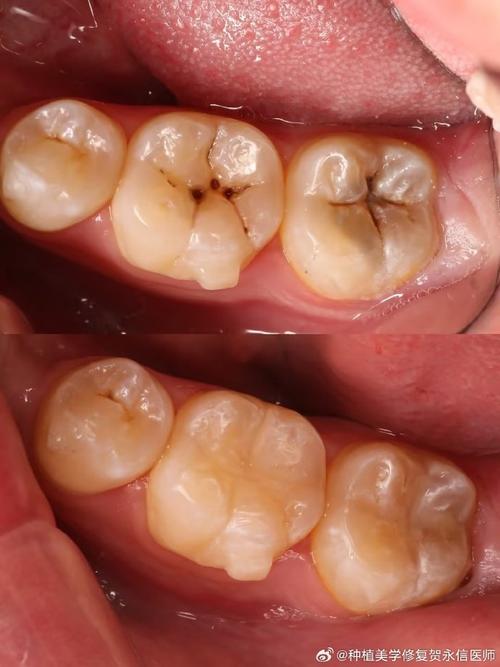

第二阶段:中期龋齿(中龋)

龋坏已经突破牙釉质,到达了牙本质层,这时,症状会变得明显起来。

- 主要症状:

- 形成明显的龋洞: 牙齿上出现肉眼可见的黑洞或棕色/黑色的龋洞。

- 对冷、热、甜、酸食物敏感: 这是中期龋齿最典型的症状,当吃到冰淇淋、热汤、甜食或酸性饮料时,牙齿会产生一过性、尖锐的疼痛,刺激去除后疼痛立即消失,这种敏感不是持续性的。

- 探诊有疼痛感: 用探针探查龋洞时,会感到明显的酸痛。

- 患者感觉:

- 主要表现为刺激性疼痛,没有自发性疼痛。